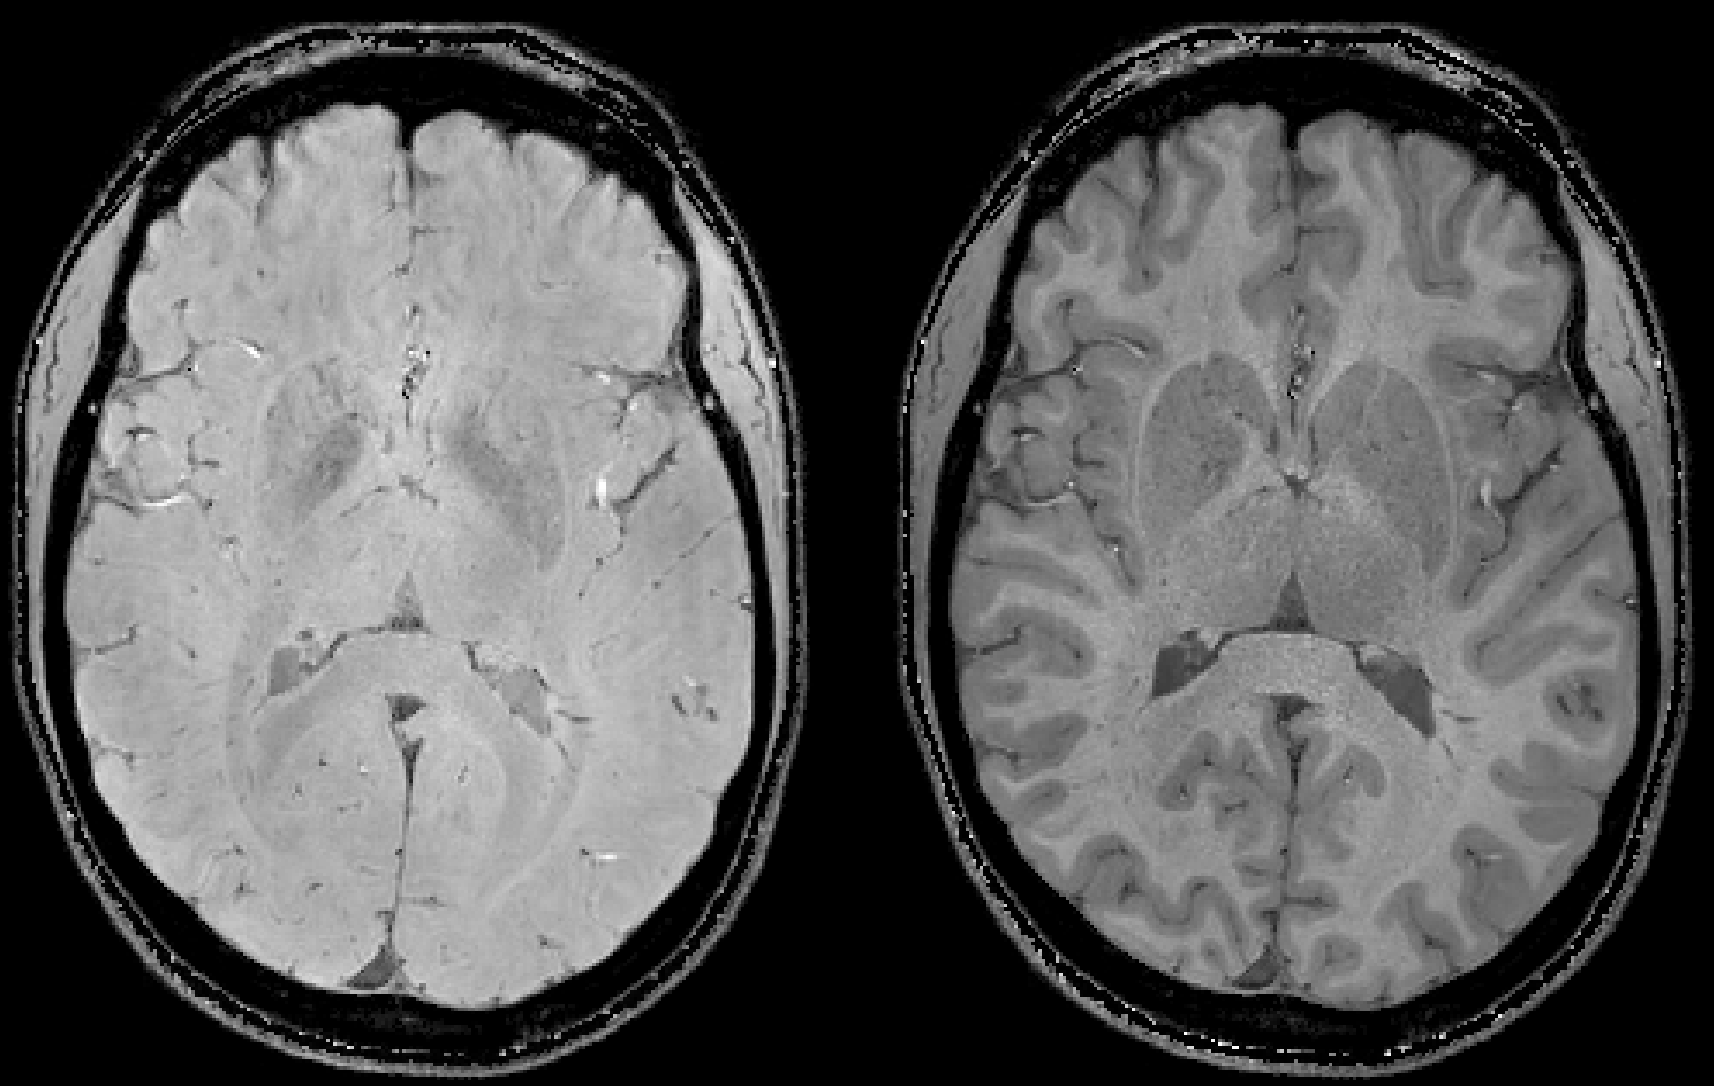

Some repesentative images including the T2starw and T1w magnitude images:

In this example, we simulated spherical susceptibility sources to generate a BIDS directory with a range of B0 directions:

On the left is the phase image with the two sources with an axial B0 direction. On the right is a phase image with the two sources with a B0 direction rotated 30 degrees about the x axis.